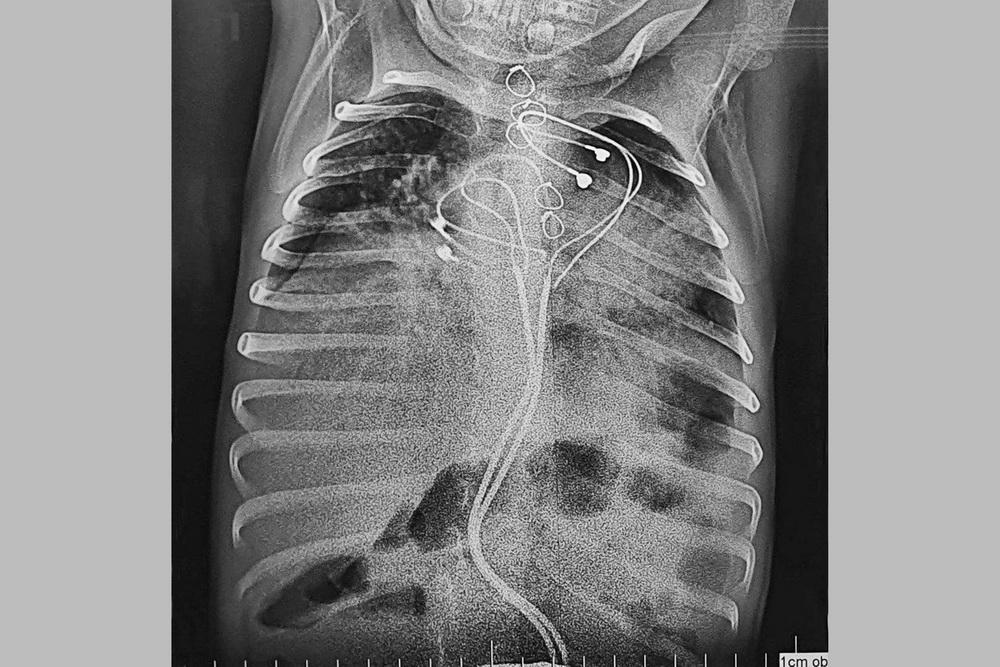

«На рентгенографии подтвердилось то, что казалось невероятным: устройство не только сумело мигрировать в брюшную полость, преодолев барьер из мышцы и брюшной стенки, но и проникло непосредственно в кишечник, продолжая при этом исправно работать и задавать необходимый ритм сердцу», — описали ситуацию в клинике.

Врачи пришли к выводу, что приспособление продвинулось по сигмовидной кишке.

Но окончательно покинуть тело оно не смогло — мешали электроды и проводки, которые тянулись от сердца. Образовался кишечный свищ, орган закупорился.

Прежде чем извлечь кардиостимулятор, на рёберно-диафрагмальную поверхность имплантировали однокамерную альтернативу. Вторым этапом стала открытая операция на брюшной полости. Сигмовидную кишку очистили от спаек, нашли место входа инородного тела и вытащили его наружу. Инфицированные электроды отсекли. Дефект кишечной стенки закрыли. После курса антибактериальной терапии на десятый день ребёнка выписали в удовлетворительном состоянии.